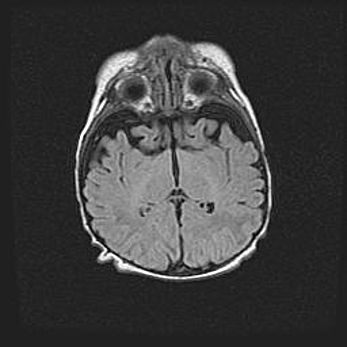

Неполная лизэнцефалия (пахигирия). Открытая гидроцефалия.

Возраст: 17 дней

Вес: 3110 г

Пол: мужской

Окружность головы: 33,5 см

Срок гестации: 35-36 недель

Лизэнцефалия—недоразвитие корковой пластинки и мозговых извилин в результате нарушения миграции нейронов коры. Поверхность мозговых полушарий гладкая. Микроскопически выявляется отсутствие нормальных слоев коры и скопление групп нейронов в подкорковом белом веществе.

Пахигирия—уменьшение числа вторичных извилин. В пораженном полушарии нервные клетки образуют толстый недифференцированный слой с неправильно расположенными нервными волокнами и группами гетеротопных клеток. Нервные клетки незрелые. Белое вещество истончено. При этом нередко аномально развит корково-спинномозговой путь.